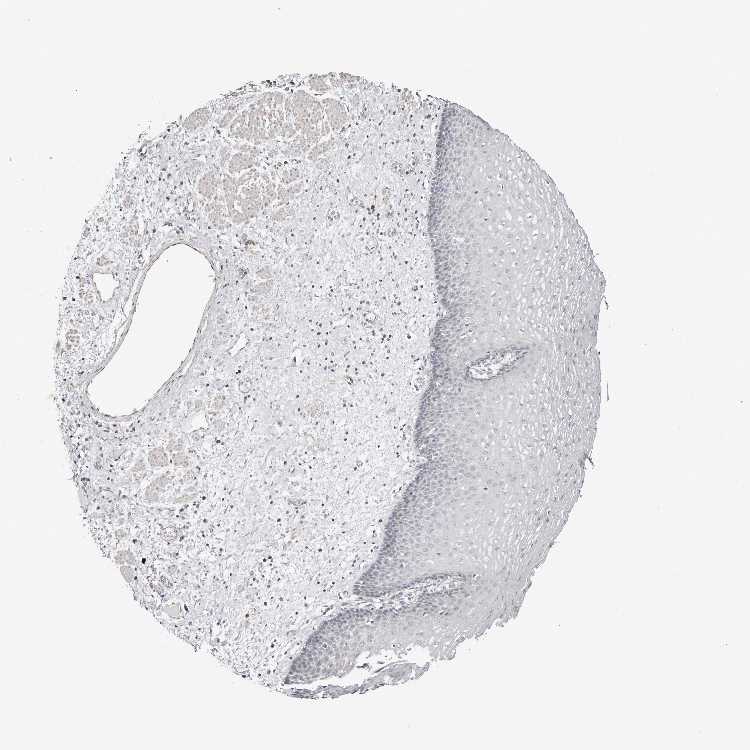

ESOPHAGUS - HPA RNA-seqi

The RNA-seq details section shows detailed information about the individual samples used for the transcript profiling and results of the RNA-seq analysis.

Information about each individual sample is listed below, including gender, age, a tissue section image and estimated fractions of cell types. nTPM (normalized transcripts per million) values give a quantification of the gene abundance which is comparable between different genes and samples.

Female, age 70

Esophagus sample 130

nTPM: 1.7

Cell types%

Squamous epithelial cells:

35

Smooth muscle cells:

15

Skeletal muscle cells:

5

Other cell types:

45

overview

Male, age 38

Esophagus sample 131

nTPM: 1.3

60

20